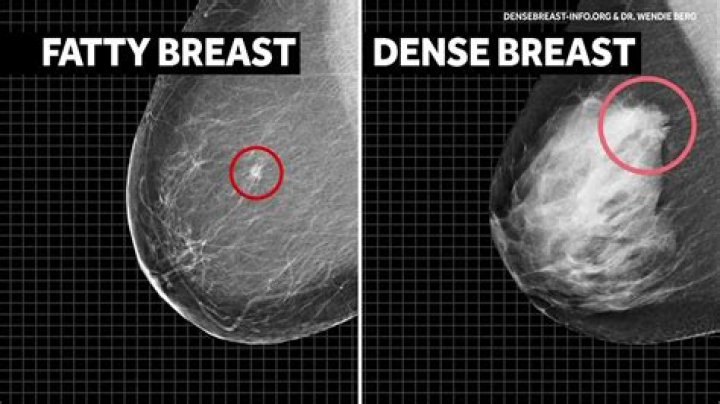

With less elasticity, the breasts lose firmness and fullness and can develop a stretched and looser appearance. It's not uncommon to change your cup size as you age. Dense breast tissue is replaced by fatty tissue as the aging process continues.